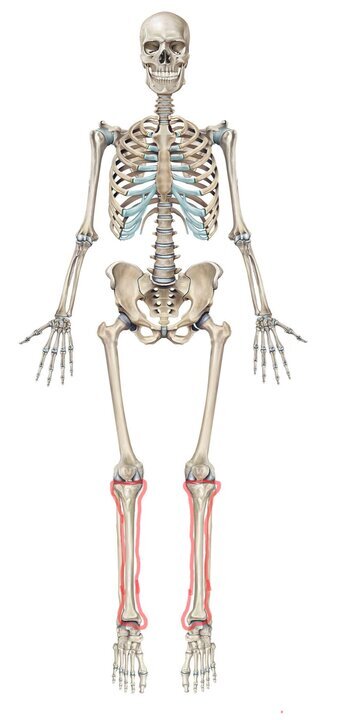

Вот большеберцовые кости в скелете.